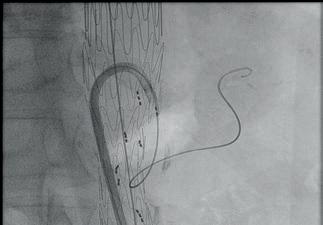

First official ESVS consensus statement consolidates expert opinion on “truly novel” aTEVAR procedure

an ageing population and increasing demand for complex endovascular aortic solutions, Santi Trimarchi (Fondazione IRCCS Cà Granda Ospedale Maggiore Policlinico, Milan, Italy) and a global team of experts recently authored a consensus statement on ascending thoracic endovascular aortic repair (aTEVAR).

The aTEVAR statement includes recommendations on patient selection, procedural strategies, and postoperative management among other areas.

“By addressing key topics such as landing zones, stent graft sizing, risk assessment, and adjunctive procedures, this document aims to guide clinical practice, improve patient outcomes, and enhance procedural safety,” Trimarchi and colleagues write in the paper.

Continued from page 1

speaking to Vascular News following the open-access publication of the statement in EJVES, notes a growing interest in this niche area. “The data are limited, but the observational evidence we do have shows that a large number of aortic lesions are being treated with aTEVAR,” he says. Trimarchi also highlights growing interest in aTEVAR from industry.

Behind these factors, Trimarchi continues, is an ageing population in need of new aortic technologies.

“Twenty years ago, the mean age of patients who had a type A dissection was about 70, 72 years of age; now, it’s shifting towards 80,” he points out. Trimarchi adds that with age comes fragility and that aTEVAR “offers these patients a chance”.

“Our aim was to try to give a framework to a topic that many people are discussing, and it was a chance to highlight the state of the art and figure out how we can move forward,” Trimarchi summarises.

A lack of evidence, however, necessitates caution. This is a point stressed by Twine and Jonathan R Boyle (University of Cambridge and Cambridge University Hospitals NHS Trust, Cambridge, UK) in an editorial accompanying Trimarchi and colleagues’ paper in EJVES. Speaking to Vascular News, Twine emphasises the “truly novel” nature of aTEVAR and the fact that “very few units are doing it at the moment”. With this in mind, he stresses the importance of “trying to harmonise” all aspects of care around the procedure and avoid “outlying practice” at this stage—which the consensus statement aims to achieve. “I hope the document reinforces that you can’t start doing these very difficult, novel procedures in isolation,”

AORTIC

Twine remarks, stressing that “there needs to be an experienced multidisciplinary team in place, careful patient selection and consent and ideally the use of a framework for implementation of new procedures.”